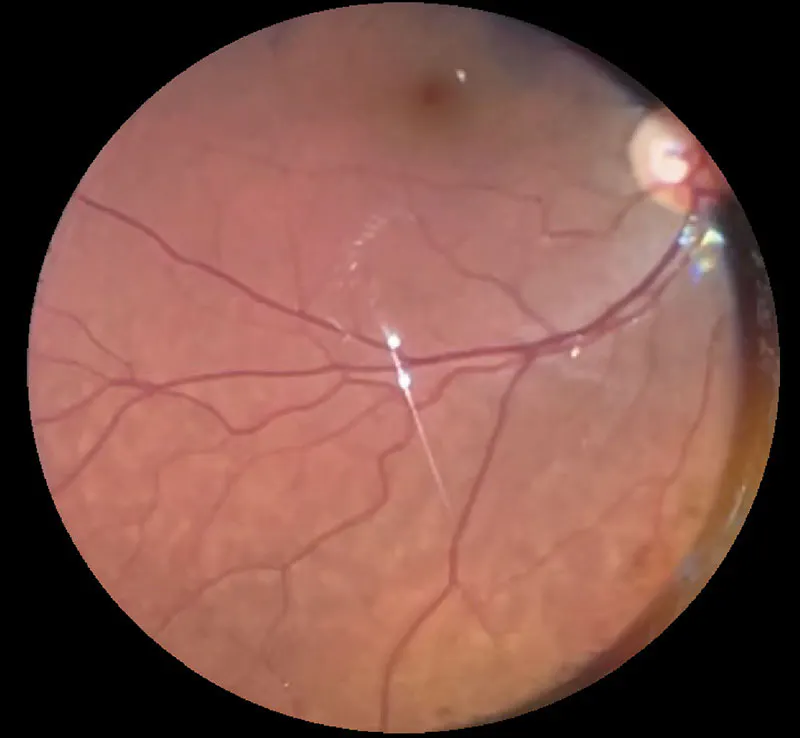

April 2026 | Pediatrics

Incontinentia Pigmenti-Associated Retinopathy

Early screening of these patients is imperative for accurate risk assessment and timely intervention.

Sengul Ozdek, MD, FEBO; and Ece Özdemir Zeydanlı, MD, FEBO, FICO